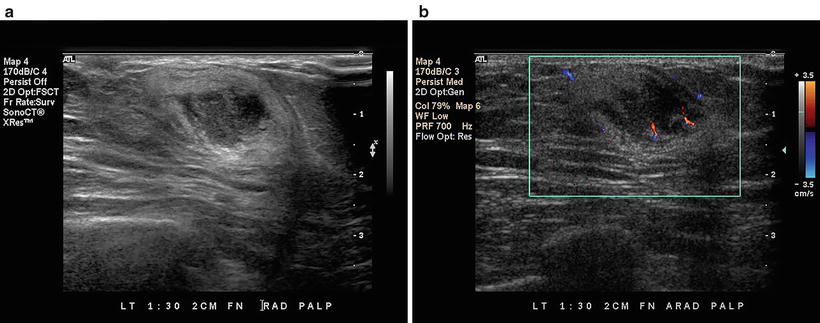

KRAS gene is the most common type of mutation reported in colorectal cancer (CRC) KRAS mutationmediated regulation of immunophenotype and immune pathways in CRC remains to be elucidated 535 CRC patients were used to compare the expression of immunerelated genes (IRGs) and the abundance of tumorinfiltrating immune cells (TIICs) in the tumor microenvironment between KRASmutant and KRAS. It is very frequent and can reach a considerable size Differentiation between lipoma and liposarcoma of low grade malignancy represents an important diagnostic problem, and valuable help in the differential diagnosis is provided by ultrasonography (US), computed tomography (CT), magnetic resonance imaging (MRI), biopsy and/or. For 30 years, Karen Minish has been sharing her gifts with the Bow Valley making us all the richer for it From sharing her incredible voice as a soloist with the Bow Valley Chorus, bringing Christmas joy through her carolling quartet, conducting the hospital choir in Banff, performing, or creating and directing the annual BVC Variety Show, creating incredible works of art, sharing her.

Ultrasound and MRI are the two major diagnostic imaging modalities for evaluating the soft tissues of the thigh Advances in ultrasound technology, including higherfrequency transducers, allow diagnosis of many types of musculoskeletal abnormalities, in many cases with an accuracy similar to that of MRI 1–4Ultrasound has additional advantages compared with MRI, such as lower cost and. Liposarcoma is a cancer that arises in fat cells in soft tissue, such as that inside the thigh or in the retroperitoneum It is a rare type of cancer that bears a resemblance to fat cells when examined under a microscope. Il liposarcoma è, tra le neoplasie della coscia, l’istotipo più comune (1240% nelle varie casistiche);.

It is very frequent and can reach a considerable size Differentiation between lipoma and liposarcoma of low grade malignancy represents an important diagnostic problem, and valuable help in the differential diagnosis is provided by ultrasonography (US), computed tomography (CT), magnetic resonance imaging (MRI), biopsy and/or. La localizzazione di partenza è quasi sempre profonda, a livello dei setti intermuscolari (in particolare per la coscia sono sedi preferenziali il m quadricipite e i m abduttori), o dai tessuti periarticolari, o dal grasso perirenale nei casi di liposarcoma retroperitoneale (5), Friedman e Egan (lO), Perry e Che (25), Edland (4), Mc Neer e. For 30 years, Karen Minish has been sharing her gifts with the Bow Valley making us all the richer for it From sharing her incredible voice as a soloist with the Bow Valley Chorus, bringing Christmas joy through her carolling quartet, conducting the hospital choir in Banff, performing, or creating and directing the annual BVC Variety Show, creating incredible works of art, sharing her.

Exosome isolation and tracking analysis EXOs were isolated from 24 h cell culture media by ultracentrifugation (UC) or ExoquickTC (EQ) (System Biosciences, Mountain View, CA, USA) methods according to standards procedures or manufacturer’s instruction, with minor modifications (Fig 1 a) For exosome purification, serum was depleted of bovine EXOs by ultracentrifugation at 100,000×g for 6. It is very frequent and can reach a considerable size Differentiation between lipoma and liposarcoma of low grade malignancy represents an important diagnostic problem, and valuable help in the differential diagnosis is provided by ultrasonography (US), computed tomography (CT), magnetic resonance imaging (MRI), biopsy and/or.